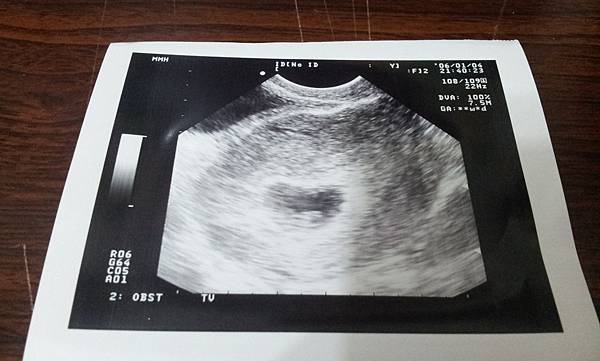

因為未滿10週需要照陰道超音波,這個實在是令人感到害羞,當然要找一個女醫生看診

當時照超音波的時候,寶寶已經有心跳嚕~ 醫生當下就說大概是七週

因為裡頭有個白點就是心臟在跳動 ^___^